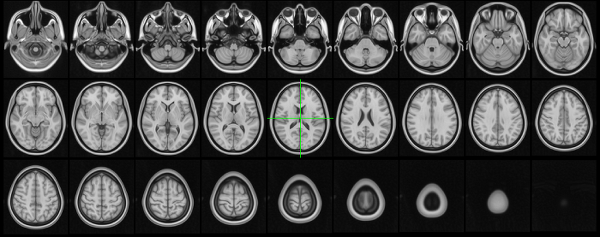

Orthographic/lightbox views

FSLeyes 1.19.0.dev10+gc3a33e578 has two primary 2D views - the orthographic (ortho) view, and the lightbox view.

Ortho view

The ortho view comprises three canvases, which display your overlays along three orthogonal planes. For a NIFTI image which is oriented acording to the MNI152 template, these canvases correspond to the sagittal, coronal, and axial planes.